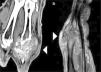

A) Se observa una tumoración de partes blandas localizada en la región dorsal de base de tercer dedo, de ecoestructura heterogénea (cabezas de flecha blanca). B) Imagen de localizador de TC: se observa que lesión destruye la cortical de la cabeza del tercer metacarpiano (cabeza de flecha blanca).

Paciente masculino de 80 años, con antecedente de hipertensión arterial controlada, acudió por presentar una lesión en la región dorsal de la base del tercer dedo de la mano derecha, de meses de evolución. En la exploración física la lesión presentaba una consistencia sólida y estaba parcialmente adherida a planos profundos, por lo que fue diagnosticada clínicamente como tumoración de partes blandas. Se decidió realizar una ecografía que detectó una masa de partes blandas con ecoestructura heterogénea (fig. 1 A). Ante estos hallazgos, se realizaron estudios de TC y RM. En estas pruebas se observó que la tumoración tenía una morfología lobulada, contenía calcificaciones y erosionaba las superficies óseas adyacentes (figs. 1 B y 2). La lesión realzaba de forma heterogénea luego de la administración de contraste intravenoso. Ante estos hallazgos, se decidió realizar una biopsia en la que se detectaron cristales de ácido úrico, lo que confirmó el diagnóstico de artropatía por depósito de cristales (fig. 3).